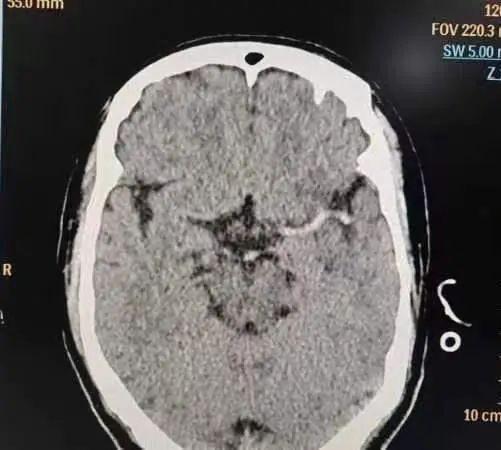

入院时,郑伯的病情已经十分严重,神经功能缺损评分高达21分(NIHSS)。医院卒中绿色通道立即为他打开,急诊科紧急组织神经内科一区医疗团队会诊,根据郑伯家属描述及症状进行了初步病情评估,并为郑伯完善颅脑CT灌注一站式检查,结果提示,郑伯的左侧大脑中动脉高密度征,左侧颈内动脉颅内段及大脑中动脉M1段不显影,考虑闭塞合并灌注不良。

▲入院急诊影像